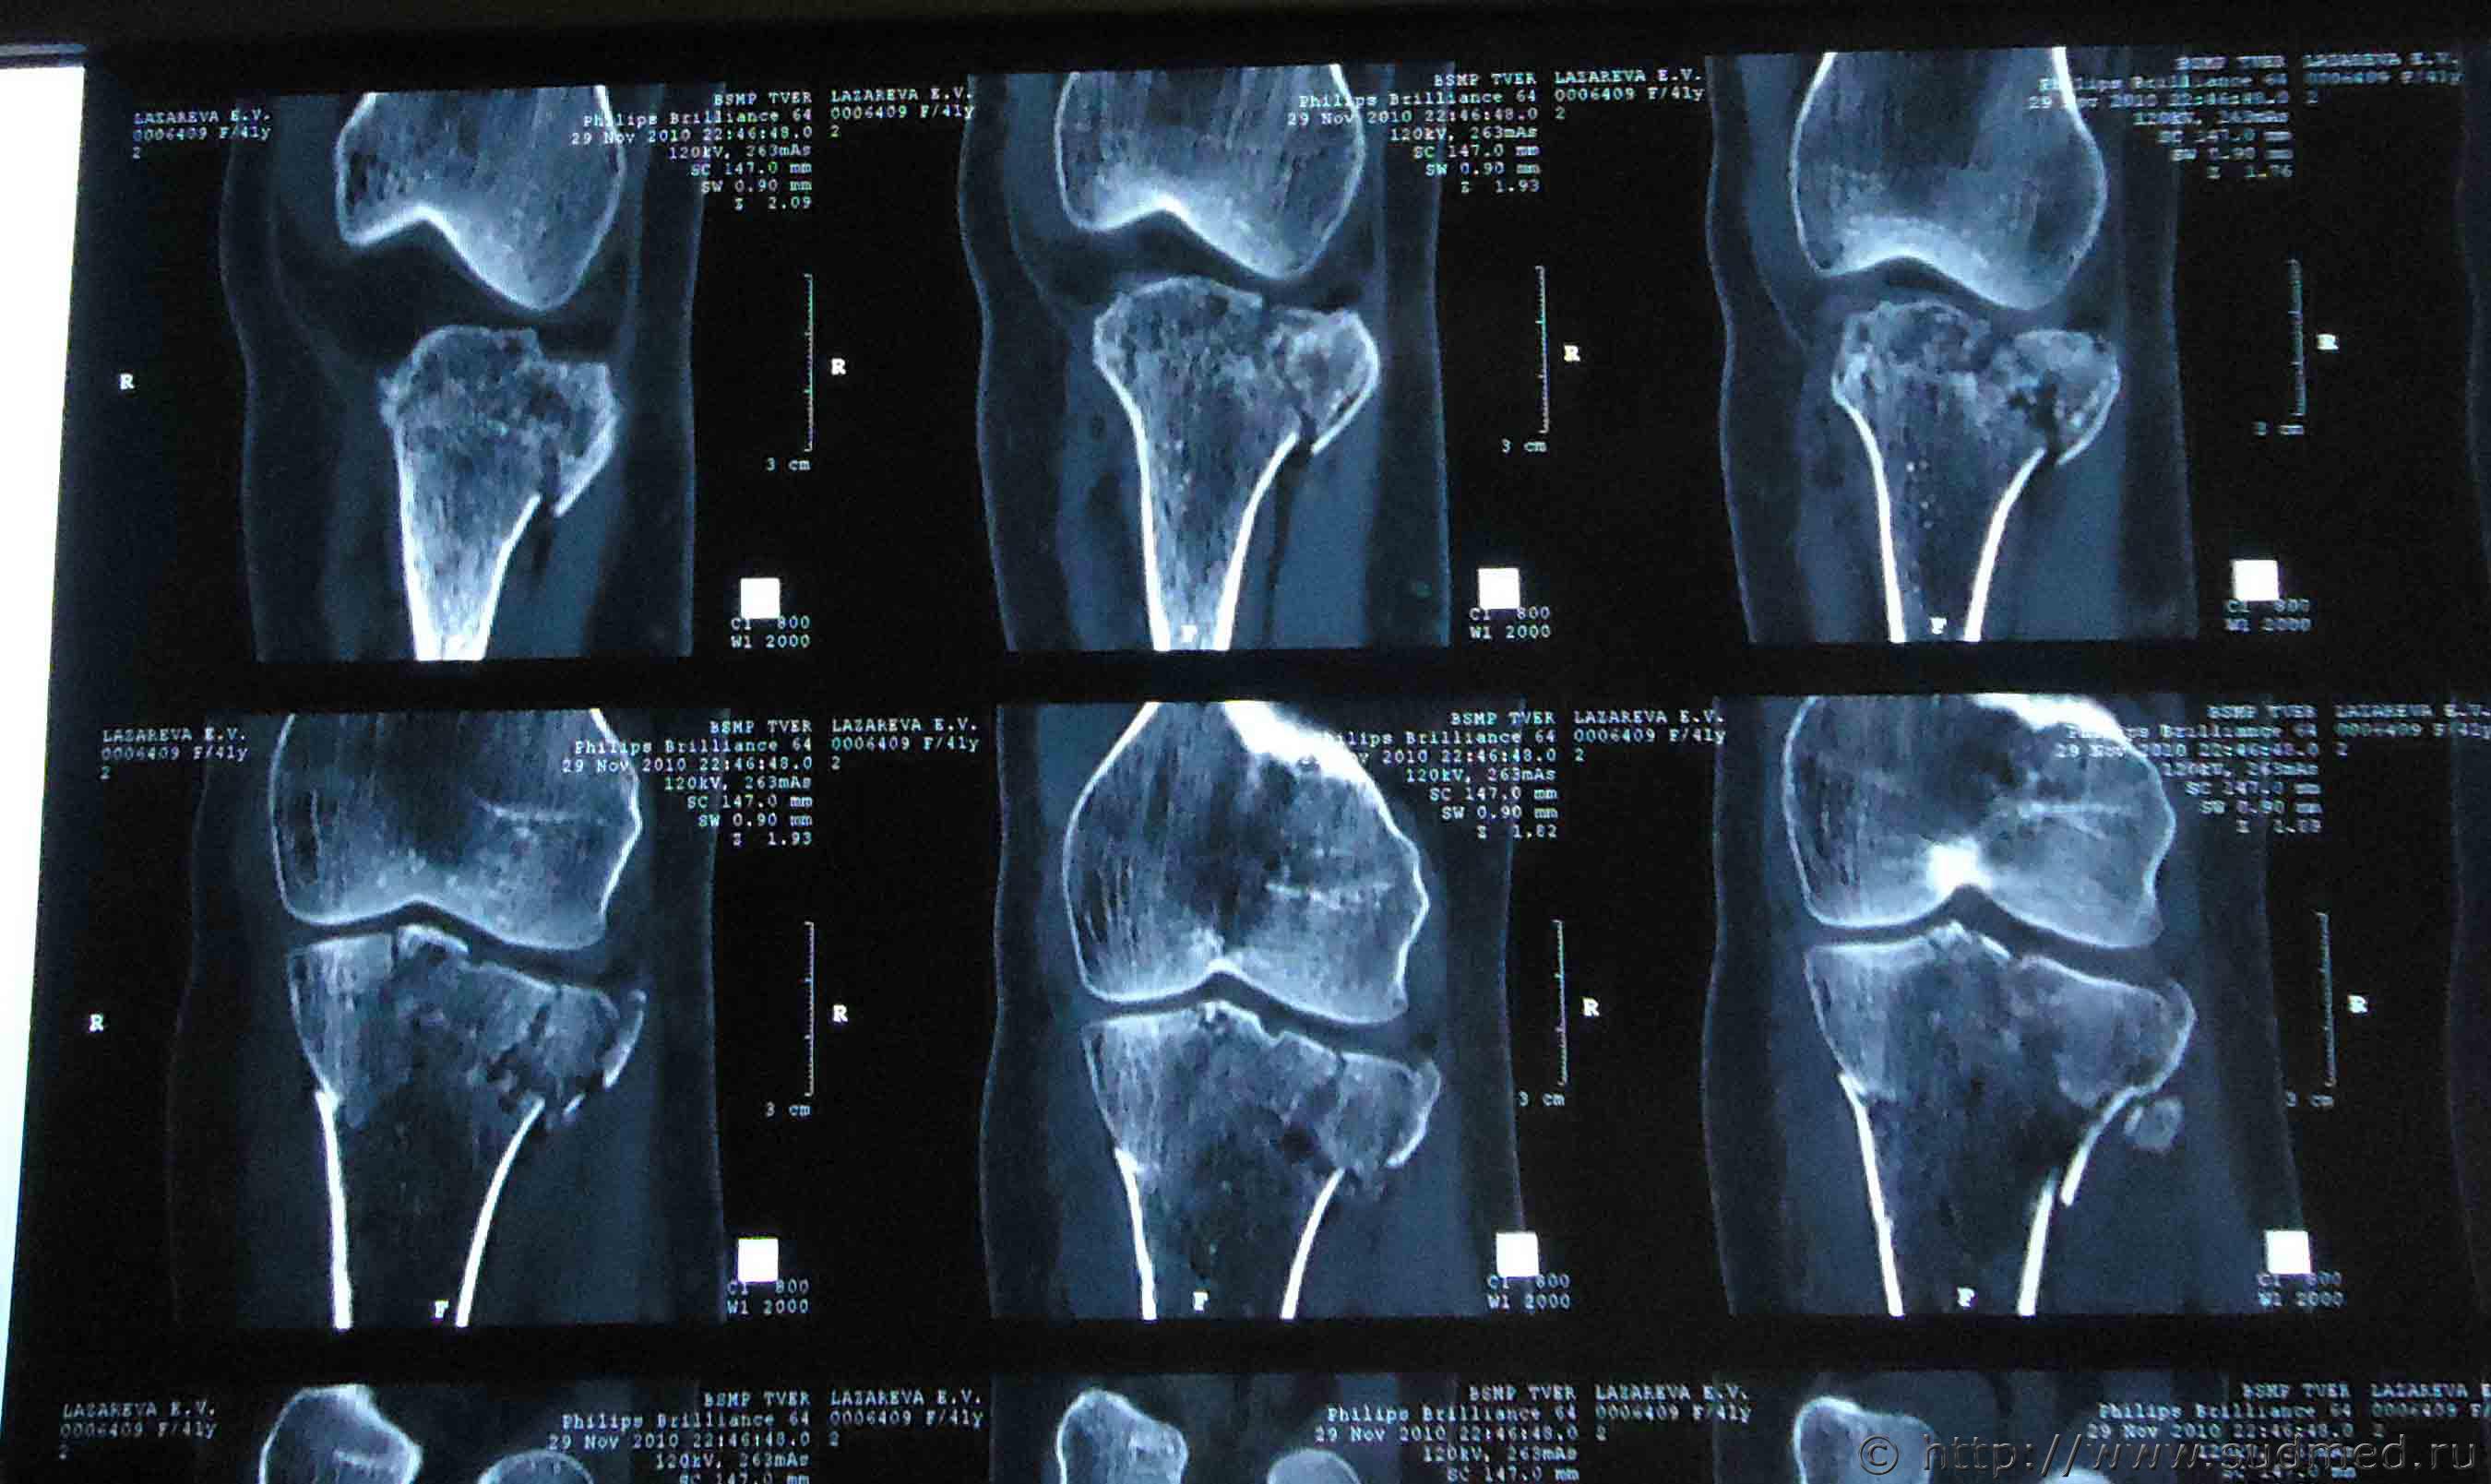

Здравствуйте. На мою жену 2 года назад был совершен наезд, при этом она получила травмы: ЗЧМТ, сотрясение головного мозга, закрытый оскольчатый внутрисуставной перелом проксимального метаэпифиза левой большеберцовой кости со смещением, закрытый оскольчатый перелом проксимального эпифиза левой малоберцовой кости без смещения, закрытый косой перелом правой ключицы средней трети со смещением отломков.

Помогите установить степень тяжести вреда и что делать для обжалования медицинской экспертизы? Снимки прилагаю